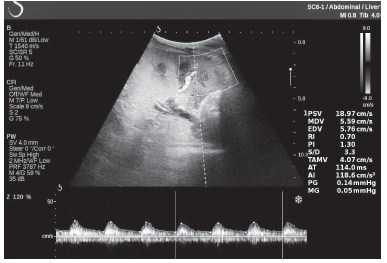

Клинический пример из второй группы. Пациент К. перенес операцию пересадки почки от живого родственного донора. Трансплантат в левой подвздошной области. Индекс резистентности в междольковых артериях составил 0,70 (рис. 5). В сегментарных артериях индекс резистентности составил 0,66 (рис. 6). Показатели жесткости паренхимы почечного трансплантата при режиме УЭСВ составили от 31,6 до 36,9 кПа (рис. 7-9).

Рисунок 5. Исследование у пациента К. в режиме цветовой и спектральной допплерографии. Индекс резистентности в междольковых артериях почечного трансплантата составил 0,70

Рисунок 6. Эхограмма пациента К. Кровоток в сегментарных артериях неизменен